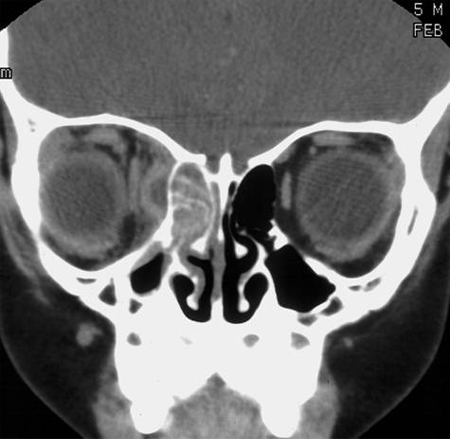

[Figure caption and citation for the preceding image starts]: Computed tomography scan with right ethmoid sinus opacification and adjacent orbital abscessFrom the collection of Melissa Pynnonen, MD [Citation ends].

CT scan with contrast is the imaging study of choice for acute rhinosinusitis with suspected complications.[1][24]

Findings consistent with, but not diagnostic of, acute rhinosinusitis include sinus opacification, air-fluid level, or marked or severe mucosal thickening.[1][24]

CT without contrast may be appropriate if invasive fungal rhinosinusitis is suspected or for bony evaluation and surgical planning, but it is not as useful as a contrast CT for detecting orbital and intracranial complications.[24]